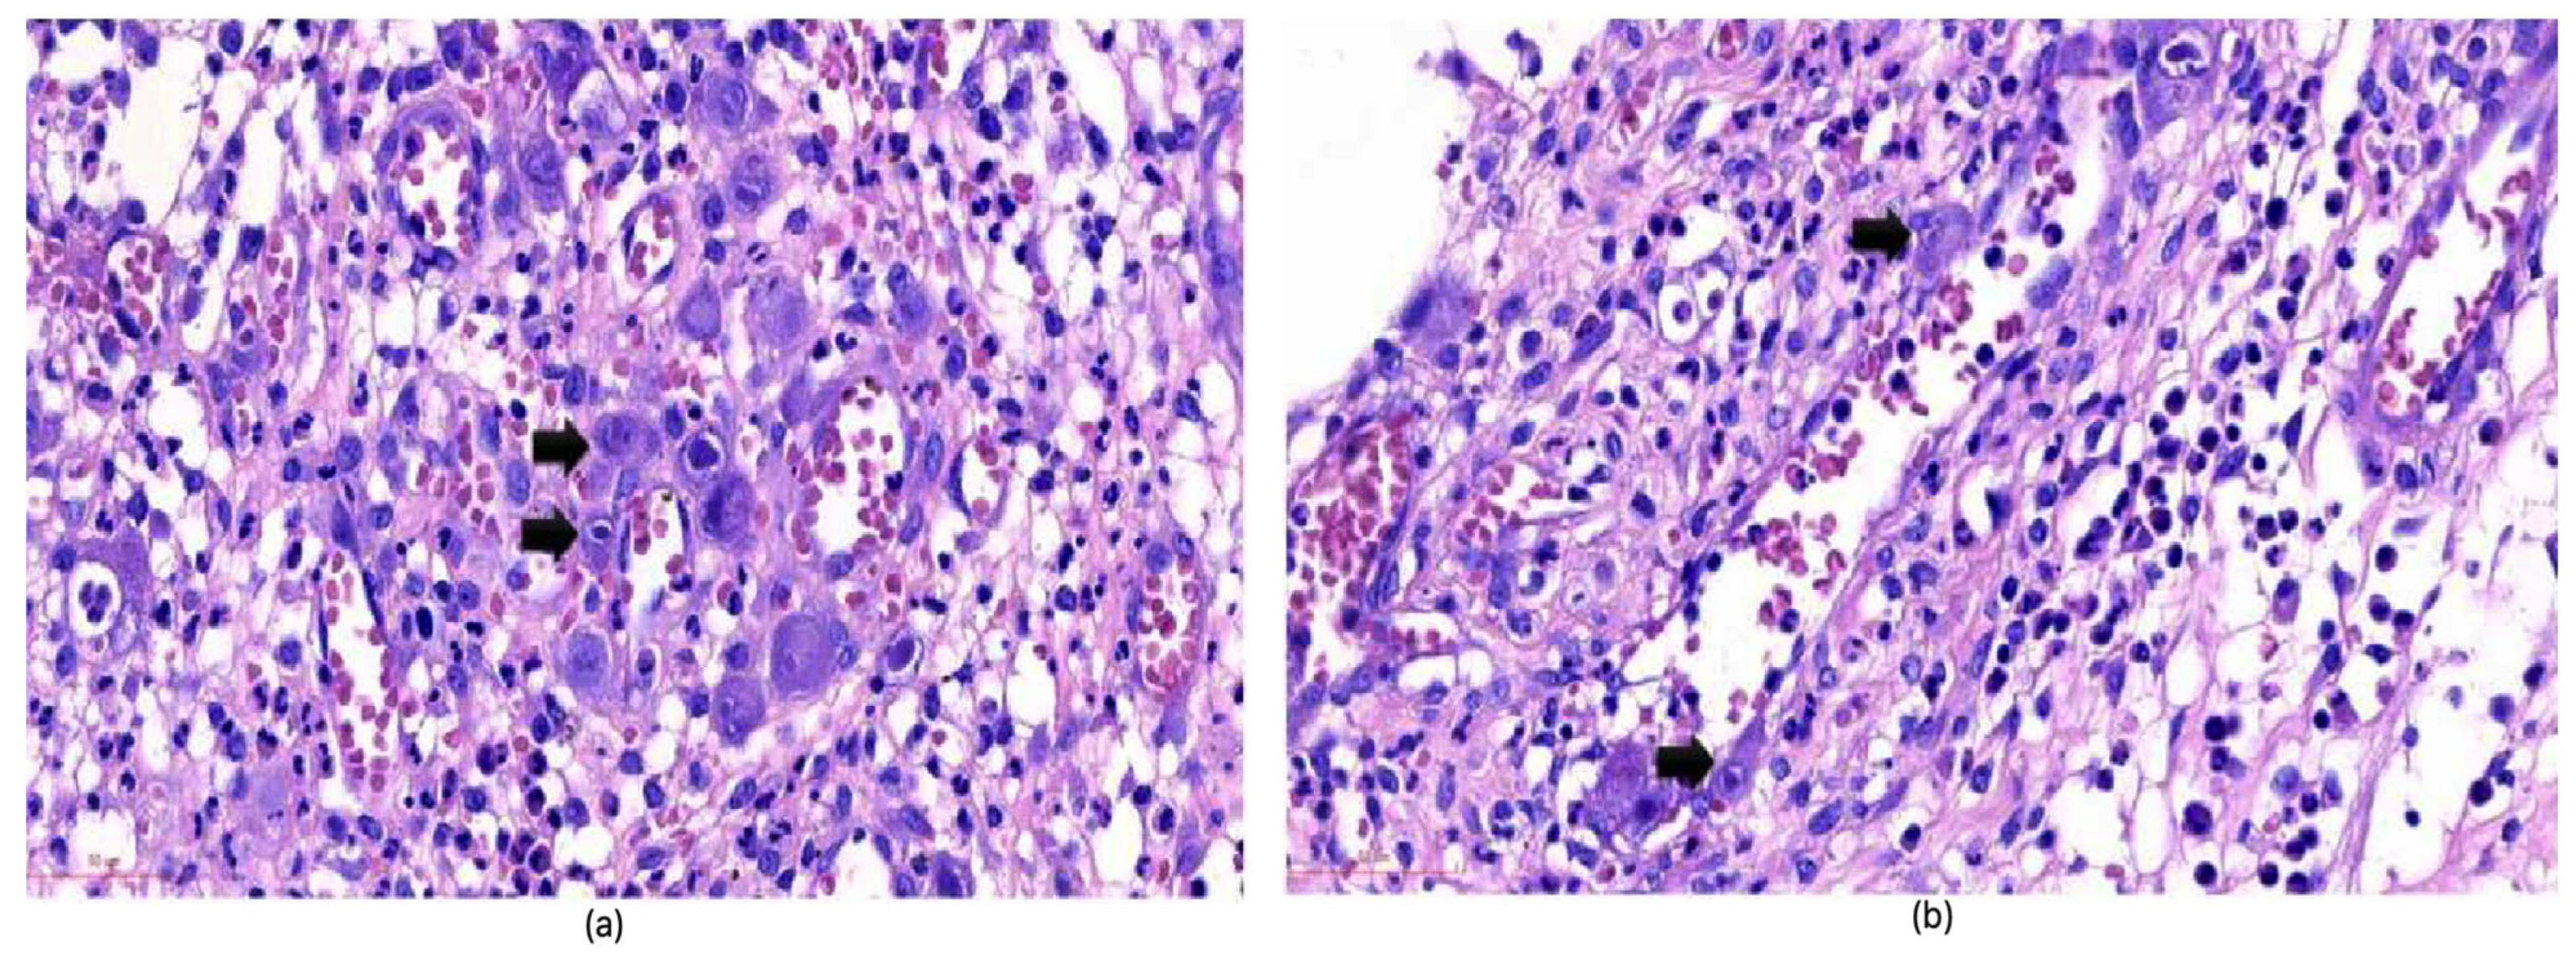

| Histology | Owl’s eye inclusions | Pathognomonic, gold standard |

| Immunohistochemistry (IHC) | CMV antigens in tissues | Sensitive and specific, gold standard |